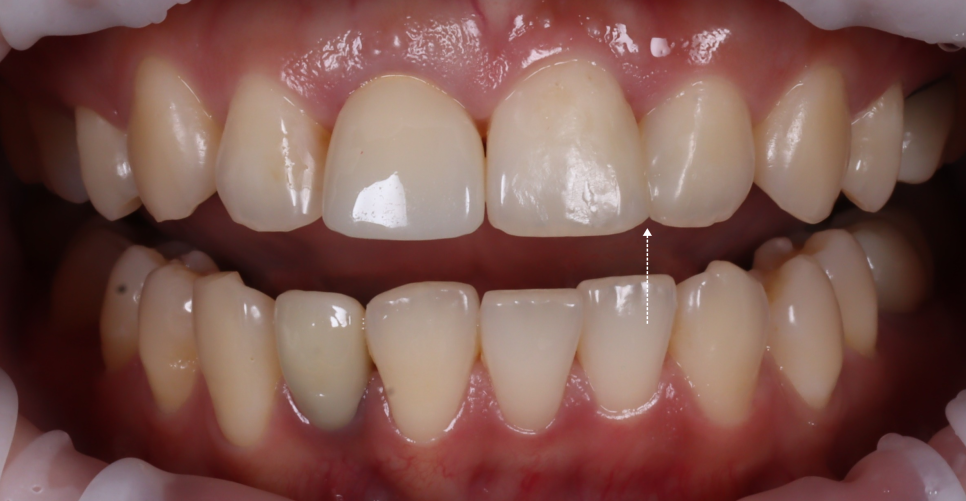

완성 후에는 치아 경계가 사라지고 자연 채광에서 봐도 거친 부분 없이 매끄럽게 보였어요.

이전의 각진 부분도 사라졌죠.

환자분이 거울을 보시면서 “와.. 진짜 감쪽같아요.” 그 한마디로 피로가 다 풀리더라고요ㅎㅎ

치료 후엔 잇몸과 치아 사이에 아주 얇은 ‘블랙트라이앵글’이 남았는데요.

자연스러운 곡선을 살리다 보면 잇몸이 완전히 닿지 않는 부분이 생겨요.

그걸 억지로 메우면 오히려 부자연스러워져요.

자연스러움을 위해 비울 줄도 알아야 합니다ㅎㅎ

광주에서 올라오셨던 환자분이 “멀리 온 보람이 있네요. 너무 마음에 들어요! 원장님~ 저 반대쪽 앞니도 치료할게요!” 치료가 끝나고 이렇게 말씀하시더라고요 ᄒᄒ

만족하셔서 다른 치료까지 맡겨주신다는 말이 저는 제일 좋더라고요ㅎㅎ